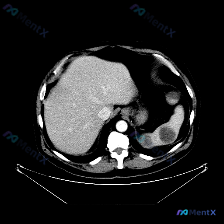

今天整理了一份上腹部增强CT的影像资料,结合临床分析思路,觉得挺有讨论价值的,分享给大家。 影像核心发现 上腹部增强扫描(软组织窗): - 肝脏:轮廓光滑,密度均匀,未见明确局灶性病变; - 脾脏:体积增大,实质内见多发圆形/类圆形低密度灶,边界相对清晰,增强后无强化或强化程度远低于正常脾实质; -...

看到一个腹部CT的病例资料,影像表现非常有特点,整理一下思路和大家分享讨论。 --- 先看核心影像表现 这是一份腹部CT横断面(软组织窗)的图像: 1. 肝脏:形态大小基本正常,实质密度相对均匀,没看到明确局灶性占位。 2. 脾脏(重点):明显增大,位置下移;更关键的是,脾实质内可见大片状、不规则的...